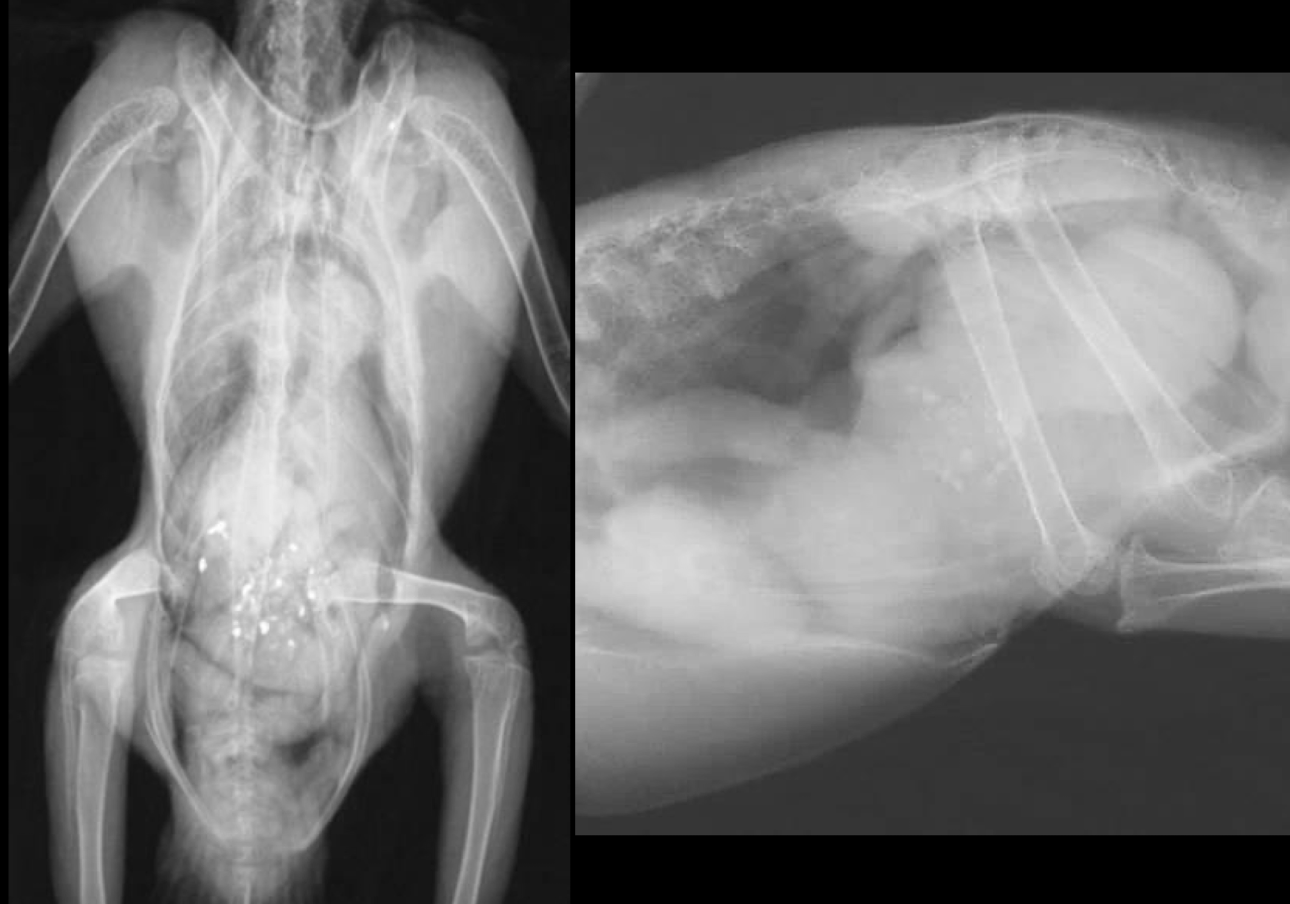

Correct radiograph positioning VD

Correct radiograph positioning Lateral

Normal avian body xray

Normal avian lateral xray